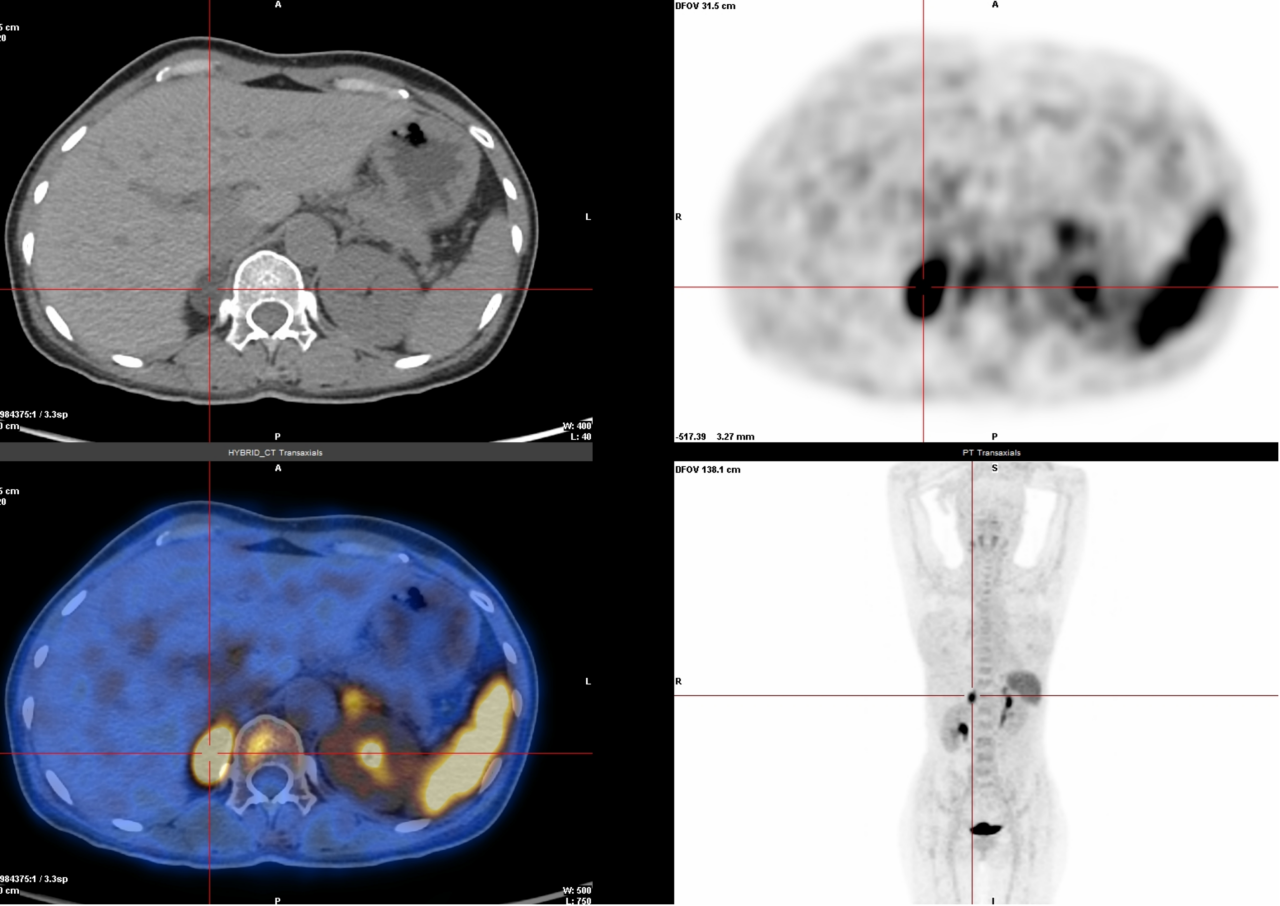

4. 醛固酮瘤、多发性骨髓瘤、惰性淋巴瘤检查(68Ga-Pentixafor):这些肿瘤表面有一种叫CXCR4的“标记物”,这种检查能精准锁定它。

△右侧肾上腺醛固酮瘤

△多发性骨髓瘤